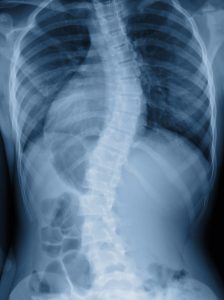

Can Chiropractors Help Severe Scoliosis?

Scoliosis, a sideways curvature of the spine, is a condition that many